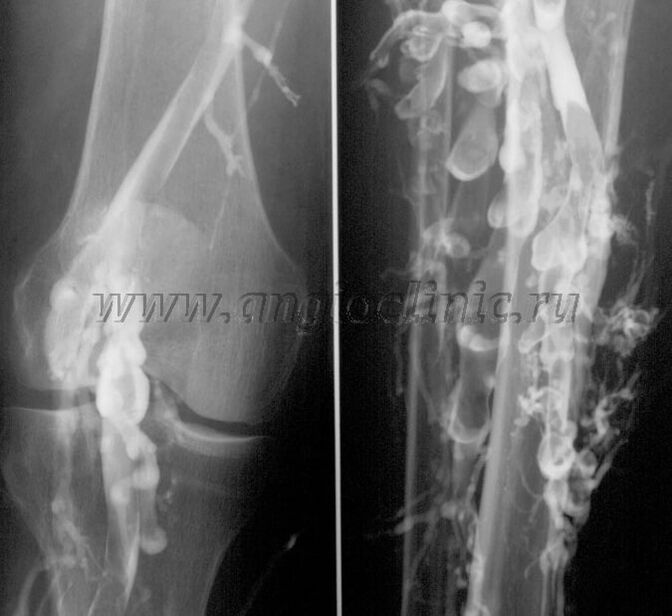

Βελογραφία αντίθεσης

Συνήθως, μια υπερηχογραφική εξέταση αρκεί για την πλήρη διάγνωση της φλεβικής παθολογίας. Ωστόσο, σε ορισμένες περιπτώσεις είναι απαραίτητο να μελετηθεί η σύνδεση μεταξύ της κατάστασης του εν τω βάθει και του επιφανειακού φλεβικού συστήματος, ιδιαίτερα σε περιπτώσεις υποτροπών κιρσών και δευτερογενών κιρσών.

Για την επίλυση αυτών των προβλημάτων, χρησιμοποιείται μια εξέταση με ακτίνες Χ αντίθεσης. Οι σαφηνές φλέβες τρυπούνται και χορηγείται σκιαγραφικό. Παρατηρείται η κίνηση του σκιαγραφικού στην οθόνη του ακτινογραφικού μηχανήματος και γίνονται όλες οι απαραίτητες δοκιμές και προβολές. Η φλεβογραφία χρησιμοποιείται επί του παρόντος πολύ σπάνια για κιρσούς.